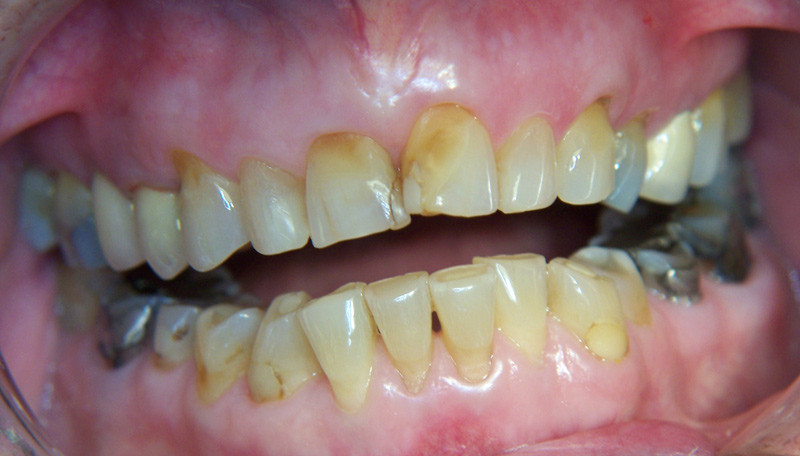

Osteonecrosis of the jaw in patients using bisphosphonates was first described in 2003 (4, 5). There appears to be a clear association between long-term use of bisphosphonates and osteonecrosis of the jaw, particularly in cancer patients who have received bisphosphonates intravenously. Evidence for this association is complicated by the fact that these patients usually have another comorbidity and take a number of other drugs such as analgesics, steroids and cytostatics. However, many cases of osteonecrosis of the jaw have also been reported in osteoporosis patients who have relied solely on peroral bisphosphonates (6). We have found no reports dealing with temporomandibular joint destruction combined with long-term use of bisphosphonates. Since bisphosphonates interfere with the metabolic mechanisms of bone, such as inhibition of osteoclast function and angioneogenesis (7), this association is not improbable.

Treatment of the bite problems in our patient appears to represent a significant challenge, in that the bite opening is too large to be corrected by dental contouring and prosthetic crown therapy. Since this appears to be an ongoing process of destruction, there is also a high probability of recurrence after this type of treatment. The most appropriate treatment would presumably be surgical reconstruction of the temporomandibular joint with rib transplants, possibly with total prosthetic replacement of the joint.

Degenerative disorders of the temporomandibular joint with changes in bite as described in our patient are very rare in otherwise healthy patients. The patient has not been exposed to injury or received medication that could conceivably be of pathogenic significance, such as corticosteroids, other hormone treatment, radiotherapy or cytostatics. We therefore consider long-term medication with bisphosphonates to be a very probable cause of her jaw and femur problems.